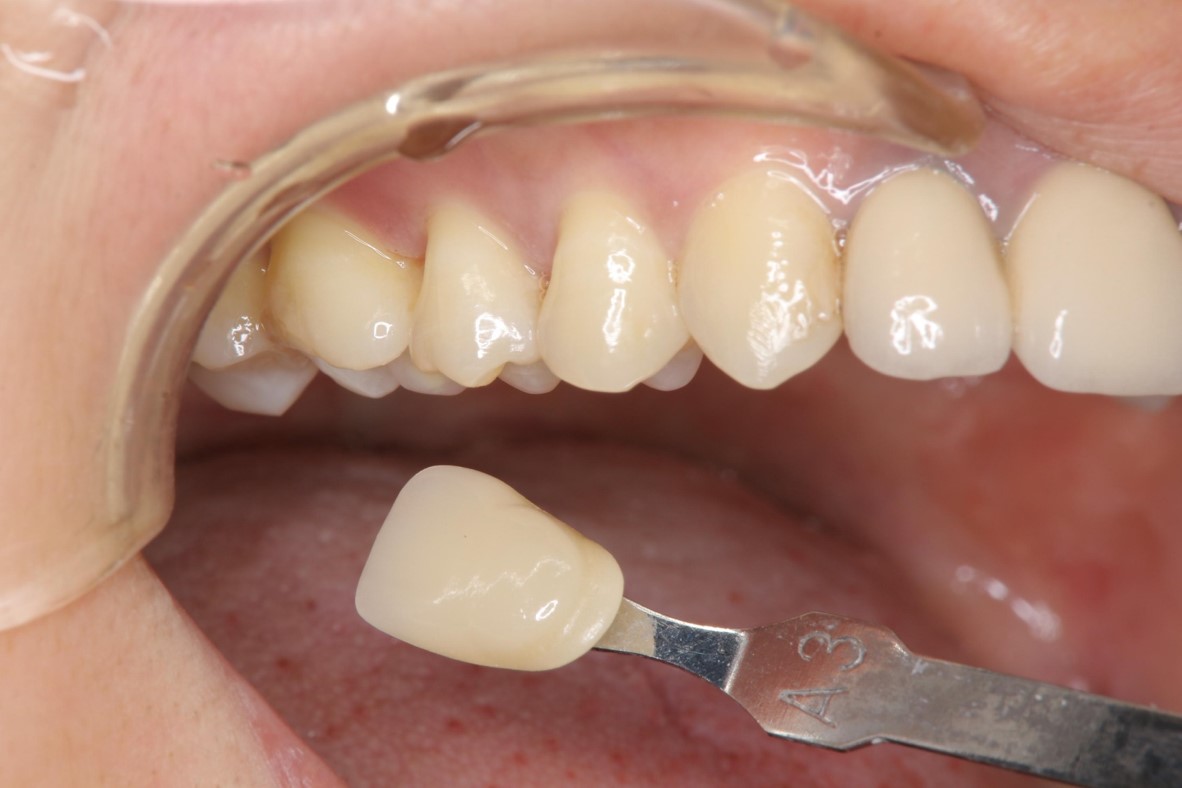

照相比色